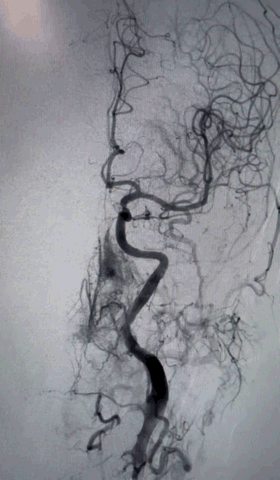

术后即刻影像及患者术后情况

最终正侧位造影见载瘤动脉通畅,动脉瘤完全不显影,远端血管显影良好。

充分评估是前提,根据手术路径,制定合理的手术方案,选择适合的通路产品。术中关键器械的选择:Skathi远端通路导管和Locaste输送导管搭配,既为近端提供强劲支撑性,又使微导管到位后,填塞动脉瘤过程中增加稳定性。为手术安全顺利结束保驾护航。